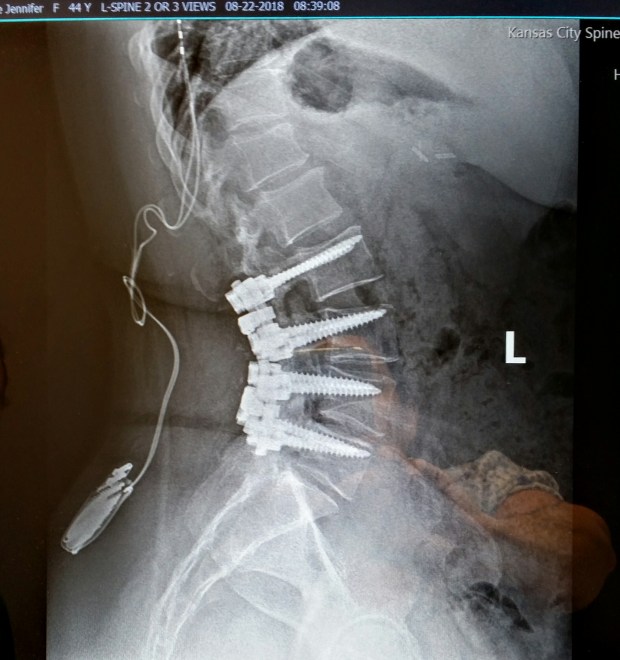

Here’s what my X-rays look like now. The little do-hickey that’s off to the side is my spinal stimulator. The battery is implanted in my hip and the wires go to the pain center of my brain. It causes a distraction, because your brain can’t fully focus on two pains at the same time. So I have this tingling, like when your foot falls asleep, only I have it from the rib cage down to my toes. It feels like wearing electrified pantyhose. No joke.

That’s from the front. And the following photo is from the side. The screws go all the way through the bone!